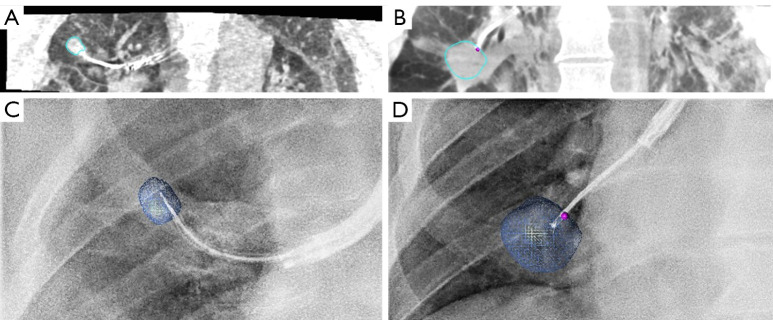

A woman with a confirmed left lower lobe adenocarcinoma presented an additional 3 mm nodule in the same lobe, too small for percutaneous sampling. Its nature was unknown, yet its location was directly relevant to surgical planning: if malignant, resection would need to be extended.

Using the Ion™ robotic platform, navigation to the nodule was achieved via shape-sensing catheter, with cone-beam CT confirming tool-in-lesion position. A Tornado coil was deployed as a fiducial marker, followed by indocyanine green (ICG) injection for intraoperative fluorescence localization.

Four days later, the adenocarcinoma was resected by segmentectomy; the marked nodule was identified via ICG fluorescence and removed by wedge resection. Final pathology confirmed a benign lesion, sparing the patient from a more extensive resection.

By characterising and marking the 3 mm nodule bronchoscopically before surgery, RAB provided the surgeon with certainty previously unavailable for lesions of this size: maximum parenchyma preservation, achieved not by accepting less information, but by acquiring more of it before the first incision.